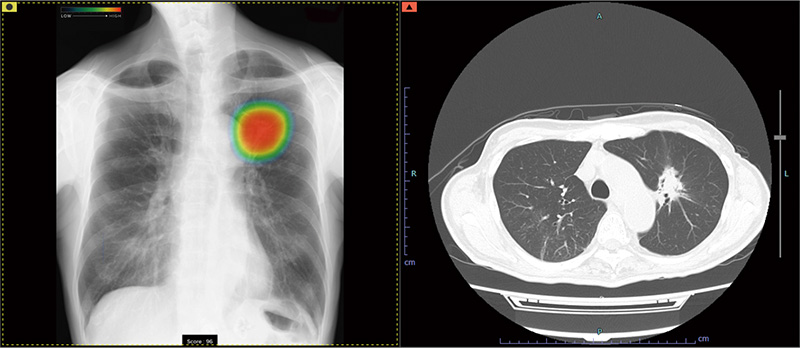

症例別ヒートマップとCTの例

当院では、富士フイルム社製の最新AI技術を搭載した画像診断ワークステーション「CarnaCore(カルナコア)」を導入しています。

このシステムでは、AIが撮影画像を瞬時に解析します。肺がんの疑いがある結節、肺炎、気胸といった見落としがちな微細なサインを自動検出し、医師の診断を強力にバックアップします。

医師による確かな読影に、客観的なAI解析を組み合わせることで、病変の早期発見と診断精度の向上に努め、より安心で効率的な診療体制を提供いたします。

• 高精度な解析: AI技術(Deep Learning)が医師の画像診断を強力にバックアップ。